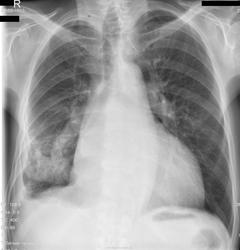

Выпот в плевральной полости справа. Затенение в S10, можно предварительно расценить как узловое образование с распадом ? ( периферический рак с распадом? осложнённый плевральным выпотом MTS). Мало клинико-лабораторных данных. Показано РКТ.

Сердце не в норме: увеличение левого предсердия, увеличение правого желудочка, признаки лёгочной гипертензии. Но есть и уменьшение объёма нижней доли правого лёгкого либо её базальных сегментов. При этом воспаление в S9, S10 не исключается, возможно и не банальное, а как проявление инфаркт-пневмонии. Выпота немного: в синусах, над диафрагмой, паракостально. Осумкован и явно не сердечный транссудат.

Хронический бронхолегочный процесс с уменьшением (цирротическим)нижней доли;Справа -плевральная спайка(но лучше уточнить на УЗИ) Компенсаторная эмфизема левого легкого;Ну конечно дилятация левых отделов сердца;Онконастороженность!

Нужно исключать онкологию, по моему сердце к этим изменениям отношения не имеет